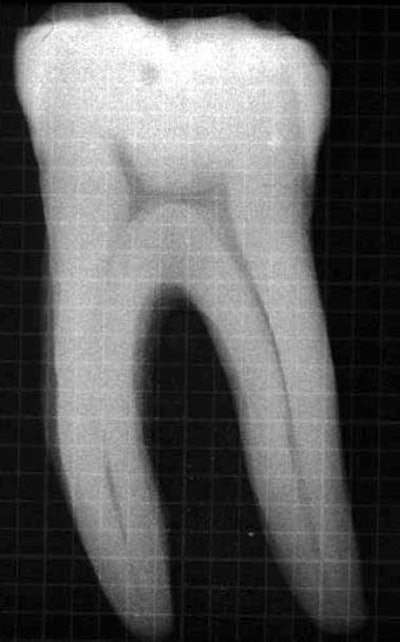

Calcified roots can not only make the instrumentation process a lot harder but also lead to perforation complications. During typical endo access with a No. 4 round bur, you can feel the bur "drop" into the pulp chamber after it passes through the harder coronal dentin.

When the pulp chamber becomes calcified, the diameter of the round bur may be larger than the pulp chamber (figure 1). This results in the clinician not feeling a difference in cutting surfaces during access. The first "drop" they may feel is the bur dropping out of the tooth and into the furcation. To alleviate this, I published a study in the Journal of Endodontics which showed that, no matter the length of the root, the mean distance from the cusp tip to the pulp chamber ceiling is just under 7 mm (mandibular molars = 6.36 mm, maxillary molars = 6.24 mm).2 Now that we know safe access should stop at 7 mm, we can develop a technique to avoid perforations into the furcation. The point on the shank of a round bur which changes from parallel to tapered is coincidently 7 mm from the tip of the bur (figure 2). Therefore, we can use the 7-mm mark as a depth gauge to more easily find the canals and avoid perforations into the furcation.